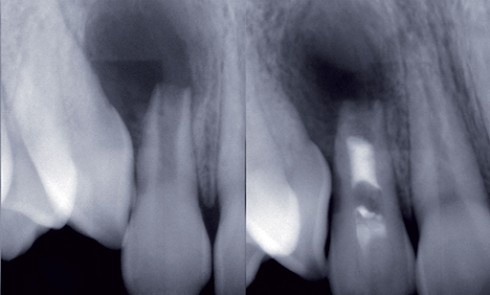

La préservation tissulaire est l’une des préoccupations majeures de la dentisterie actuelle [1]. Mais cette préservation n’est pas limitée à...La demande orthodontique du patient adulte

Bien que le traitement endodontiqueconventionnel soit considérécomme une technique validée et au pronostic acceptable, il apparaît que la régénération de...Facettes en céramique et gingivectomies : une approche a minima